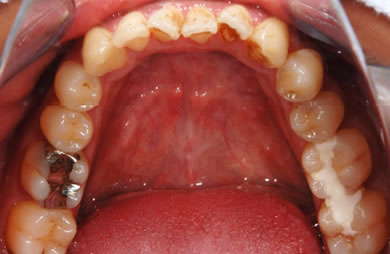

| 性別/年齢 | 男性 / 29歳 | ||||||||||||||||||||||||||||||||

| 主訴 | 歯並びを綺麗にしたい。奥歯の銀歯が目立つので白くしたい。 | ||||||||||||||||||||||||||||||||

| 治療方針 | 上の前歯部に関しては審美的回復の優先を切望されているため、透明感のあるオールセラミックのハイクオリティタイプを使用。 | ||||||||||||||||||||||||||||||||

| 治療内容 | オールセラミック(ハイクオリティ)3本、ハイブリッドセラミックインレー10本 | ||||||||||||||||||||||||||||||||

| 総治療費 | 714,286円 | ||||||||||||||||||||||||||||||||

| 治療期間 | 7ヶ月 |